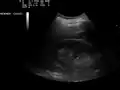

Ultrasound of liver (left side of the image) and right kidney (right side of the image) and Morison's pouch, not containing fluid -

Ultrasonographic view of the abdomen demonstrating fluid within Morison's pouch -